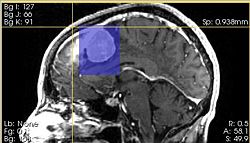

ChangeTracker analysis results

ChangeTracker greetings

ChangeTracker is a software tool for quantification of the subtle changes in pathology. The module provides a workflow pipeline that combines user input with the medical data. As a result we provide quantitative volumetric measurements of growth/shrinkage together with the volume rendering of the tumor and color-coded visualization of the tumor growth/shrinkage.